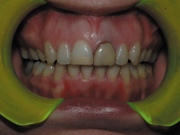

RESTORATIVE CHALLENGE: The 34-year-old female patient wanted to improve the esthetics of her teeth which were compromised by a large filling in tooth #8 and severe discoloration on tooth #9 caused by trauma and improper restoration following a root canal (see Figure 1). The patient wanted the restorations within a week but also wanted the best esthetics available.